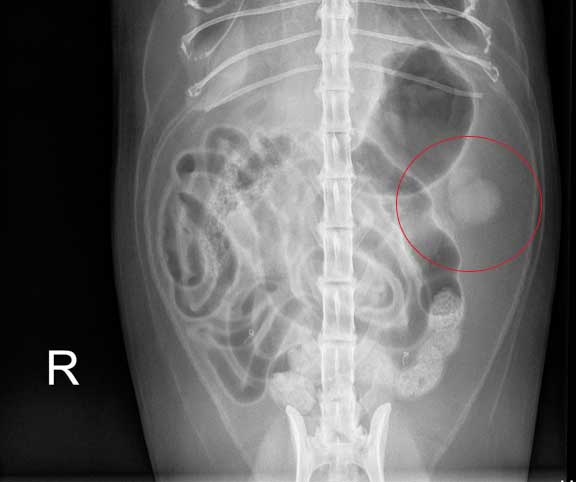

The shrunken left kidney is circled. This is common in Chronic Kidney Disease (CKD) in cats.

Food in the stomach under the circle. Look at the kidneys- notice the summation where they overlap?